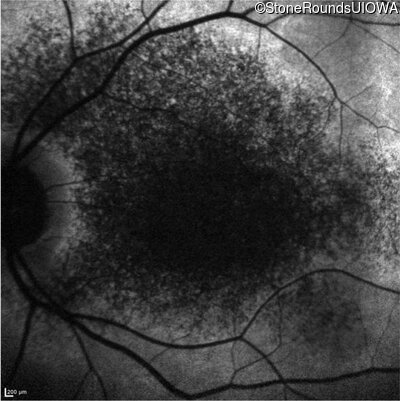

This 14 year old male began having trouble reading before the 1st grade. His parents noticed that he would not look directly at anyone.

| Disease | Gene | Allele 1 variant(s) | Allele 2 variant(s) | Inheritance mode |

|---|---|---|---|---|

| AR Stargardt Disease | ABCA4 | Ala1038Val GCC>GTC / Leu541Pro CTA>CCA | IVS36+3 del4tAAGT | AR |